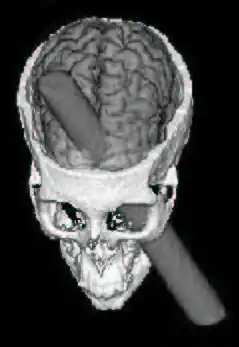

В 1848 г., когда он работал бригадиром взрывников на прокладке железной дороги в Вермонте, лом, которым он уплотнял пробку над использовавшимся при взрывных работах пороховым зарядом, высек искру и вызвал взрыв. Металлический стержень диаметром 1,25 дюйма (3,2 см) вошёл в череп Гейджа ниже левой глазницы, выходное отверстие раны располагалось на границе лобной и теменной костей также с левой стороны. Из-за ранения строитель лишился большей части лобной доли левого полушария головного мозга. Несмотря на столь тяжелые повреждения, пострадавший пришёл в сознание спустя несколько минут, но все-же был доставлен в больницу. В больнице его состояние ухудшилось так как в рану попала инфекция, но уже через два месяца он смог выздороветь и вернуться к активному образу жизни.[1]. В конце концов он оправился от инфекции, развившейся в ране, и прожил ещё 12 лет.

Считается, что эта травма привела к настолько значительным негативным изменениям в его эмоциональном состоянии, социальных навыках и личностных особенностях, что друзья заявляли о том, что «это больше не Гейдж». В мае 2012 г. были опубликованы результаты исследований группы американских неврологов, которые объяснили изменения психики Финеаса Гейджа после травмы головы[2]. Современные исследователи смоделировали полученную Гейджем травму на основании данных компьютерной томографии черепа американца, который в настоящее время хранится в анатомическом музее Медицинской школы Гарвардского университета. Для оценки повреждений коры головного мозга и располагающихся в зоне ранения проводящих путей ученые использовали современные изображения мозга 25-летнего правши, полученные методом диффузной тензорной визуализации. Таким образом исследователи выяснили, что в результате травмы Гейдж утратил около 4 % коры, а также почти 11 % белого вещества мозга. Несмотря на то, что кора была повреждена лишь в области лобной доли левого полушария, одновременно были нарушены его связи с левой височной и правой лобной долями, а также лимбической системой. Именно этим ученые объясняют изменения психики и поведения Гейджа[1].